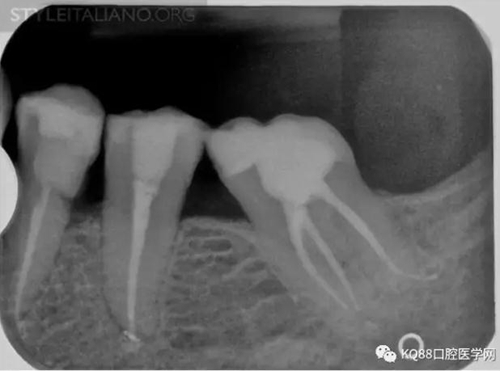

Img. 3 - The frequency of post-endodontic pain is higher in teeth with periapical or periradicular lesions. Infected debris can be forced in the periradicular tissue through a resorpted apex, thus generating acute inflammation. Creating a glide path prior to instrumentation and using a step-down technique can reduce the amount of extruded debris.